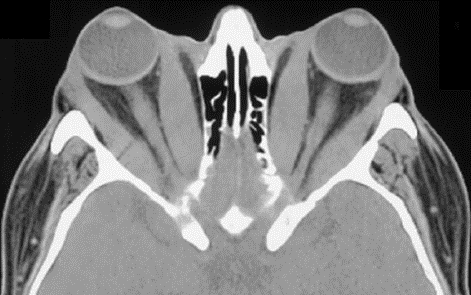

众所周知,甲状腺功能亢进(甲亢)是由于甲状腺激素分泌过多导致的疾病,男女均可发病,以中青年女性较为多见。其主要临床表现是多食易饥、消瘦、怕热多汗、心悸、易激动等,其中恶性突眼症状(如图2)就是甲亢的常见表现之一,很多患者来医院就诊的首要原因即畏光、眼睑水肿、视力减退,眼球活动度下降,容易疲劳等。

武打明星李连杰先生不幸罹患甲亢,疾病不仅影响了他自己的生活,也几乎摧毁了他的影视事业,而且深受疾病影响的他,外貌发生了翻天覆地的变化(如图3)。这种状如憨豆先生的招牌大眼睛在医学上有个专业名词,即甲状腺相关性眼病(thyroid associated ophthalmopathy, TAO)。甲状腺相关性眼病的具体表现:眼球突出,眼白外露,看起来怒目圆睁;患者眼部会感觉有明显的异物感,眼睛干涩胀痛,同时可能还伴有畏光、迎风流泪、视野范围缩小,球结膜充血等症状,严重时还会出现复视,即视物有重影,视力下降明显,进展迅速或病情危重者甚至可引起失明。总之,突眼是甲状腺功能亢进的典型表现之一,不仅危害着患者的身心健康,还严重的影响了患者的外观、外貌,让患者痛苦,严重者甚至危及生命。